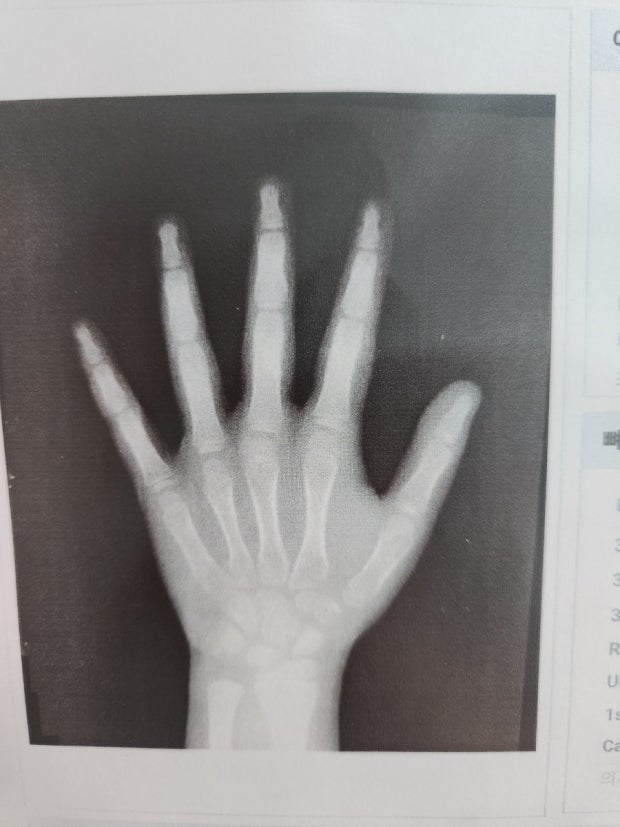

팔이나 손목 부위의 엑스레이를 촬영해 성장판(골단판)의 개방 여부를 확인하고, 이를 통해 앞으로 얼마나 더 클 수 있을지를 분석합니다.

- 왼손 손목 X-ray 촬영 (방사선량 적음)

- 뼈 나이(Bone Age) 판독 → 현재 연령 대비 성장 예측